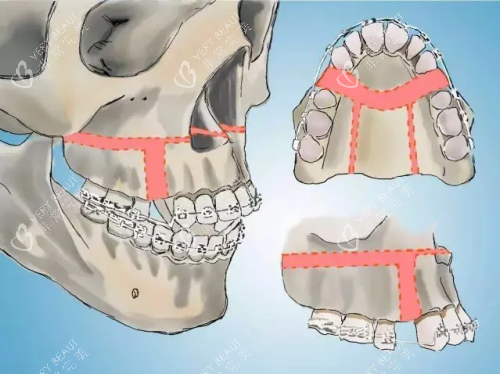

四、牙模分析:你的牙齿会"说话"!

"医生拿着我的牙模研究了半小时,说我有深覆颌伴舌倾,必须调整咬合平面。"26岁的小陈这才知道,原来牙齿的"小秘密"全藏在牙模里。

牙模能告诉你什么?

牙齿排列是否整齐

咬合关系是否正常

牙弓形态是否协调

牙齿倾斜角度

智能化牙模分析更出色,能:

模拟术后咬合关系

计算需要移动的距离

预测面部轮廓变化